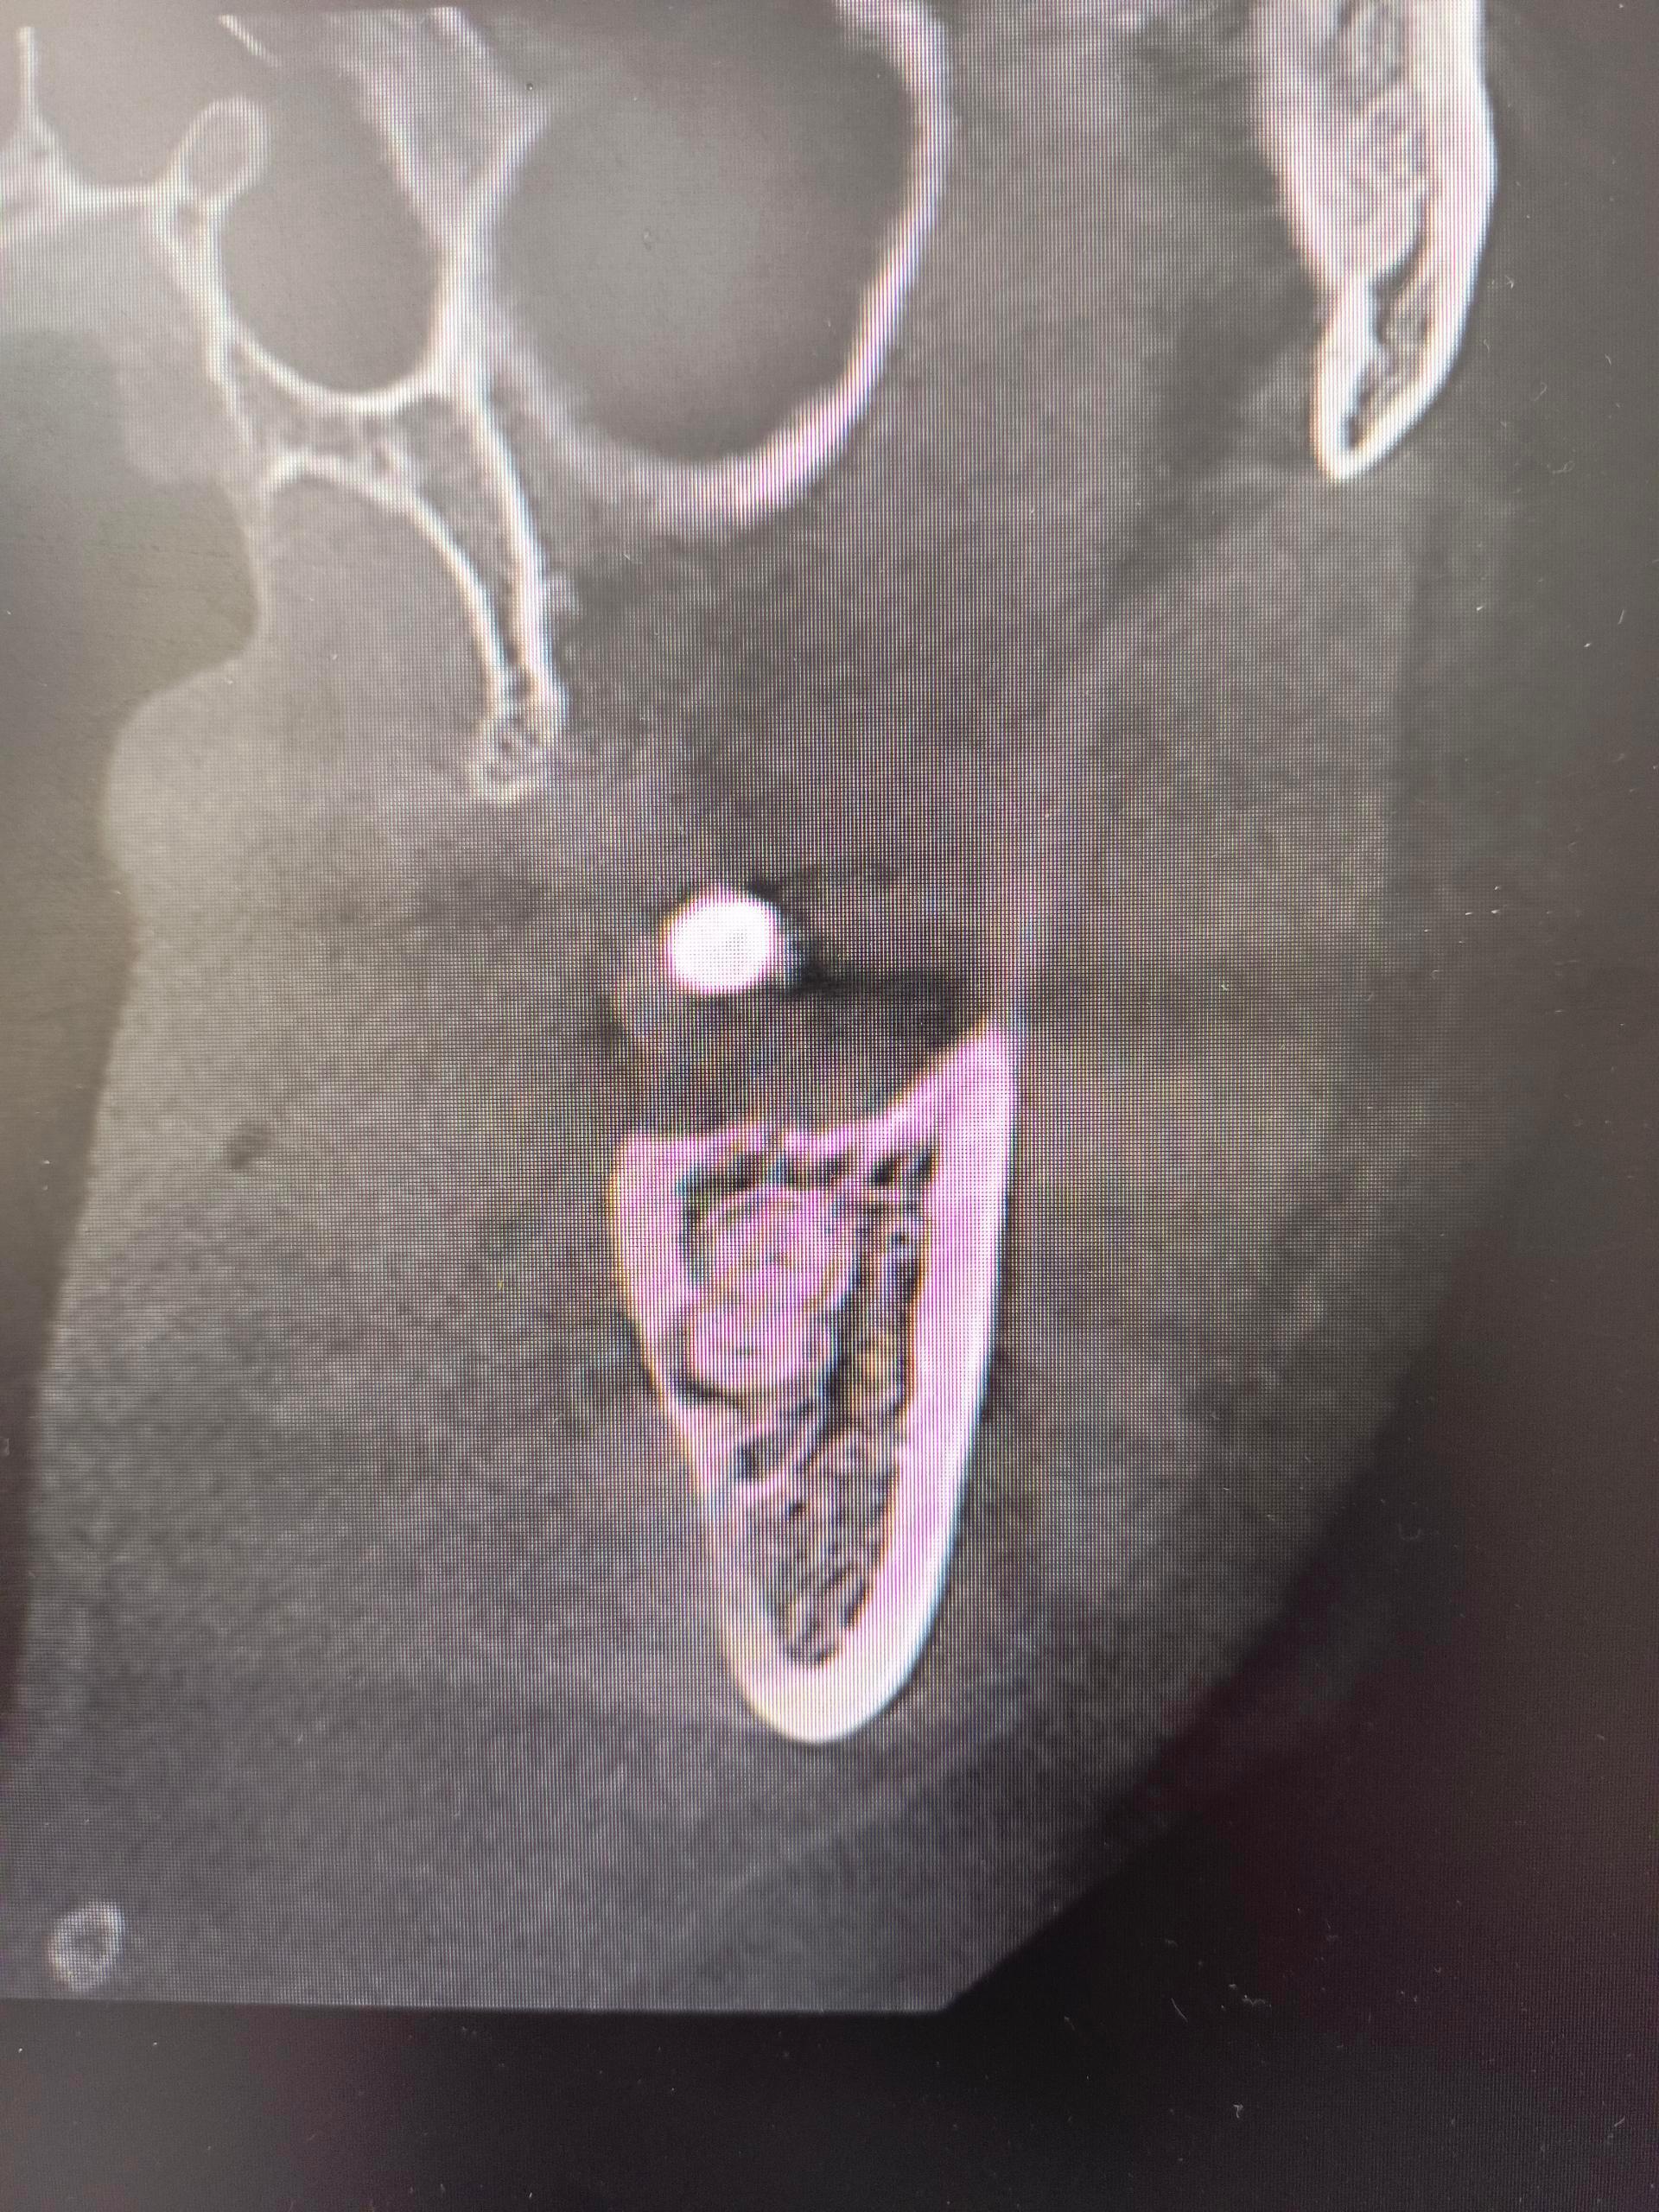

种牙和拔牙哪个更疼? 我的牙从补牙到打桩镶牙冠,再到桩子折牙冠脱落,历经8年,现在大夫让我拔牙然后种牙,我很怕疼。 拔牙犹豫了一个月,终于下决心下个月拔了吧,但还是纠结种牙或者义齿,但大夫说义齿要有挂钩在前后牙,会对它们产生伤害的。 不管怎么说也要拔牙三个月以后再决定吧。[捂脸]